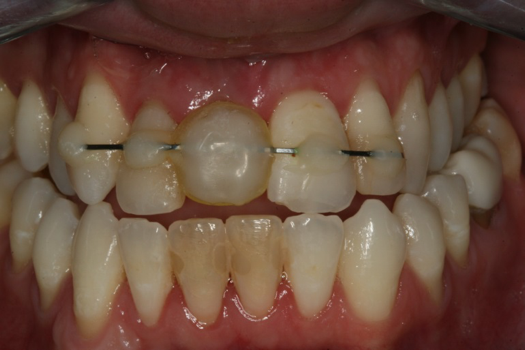

The provisional abutment and treatment crown were fabricated in the laboratory with the digital proposals. Platelet-rich fibrin (PRF) clot technology was incorporated to help with soft- and hard-tissue healing (Figure 19 through Figure 21). The screw-retained provisional and the PRF clot were seated immediately after implant placement (Figure 22 and Figure 23). One 4-0 polytetrafluoroethylene suture was placed to maintain papilla. The teeth immobilization splint was placed for 6 weeks (Figure 24). The rationale for splinting teeth Nos. 6 through 10 was due to noticeable plus-2 mobility of the remaining anterior teeth. The provisional implant crown also was included in the splint.

The young man was evaluated at 2 weeks (Figure 25 and Figure 26) and again at 6 weeks (Figure 27). The remaining natural teeth and the implant were stable. The natural teeth had a reduction in mobility to plus 1 at most. The patient's expectation was met. The soft-tissue element of his smile was maintained, and the patient is considering more cosmetic dentistry to optimize his smile. At 16 weeks postoperatively, the radiograph suggested that the digital workflow provided a great benefit to the patient and reduced the amount of chair time in the dental practice, with help from digital technology and the dental laboratory (Figure 28).

Fig 23. Provisional seated into position.

Figure 23

Fig 24. Immobilization splint placed after surgery, to be worn for no more than 6 weeks.

Figure 24

Fig 26. Postoperative at 2 weeks.

Figure 26

Fig 27. Postoperative at 6 weeks.

Figure 27